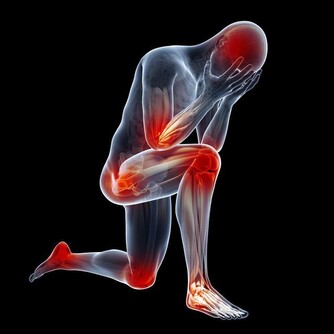

目前,患痛風的人越來越多,尤其是很多年輕人,不健康的生活習慣導致尿酸值越來越高,痛風發作的時候嚴重影響生活質量。然而,很多的痛風患者只是在盲目的降尿酸,並沒有弄清楚自己的尿酸為什麼會高,

如果你生活健康,沒有大量攝取啤酒、動物內臟、海鮮、濃茶等,最後尿酸值還是居高不下,還有一個重要的原因是——藥物性痛風,即很多藥物能夠導致尿酸高,今天就讓我們一起了解一下。